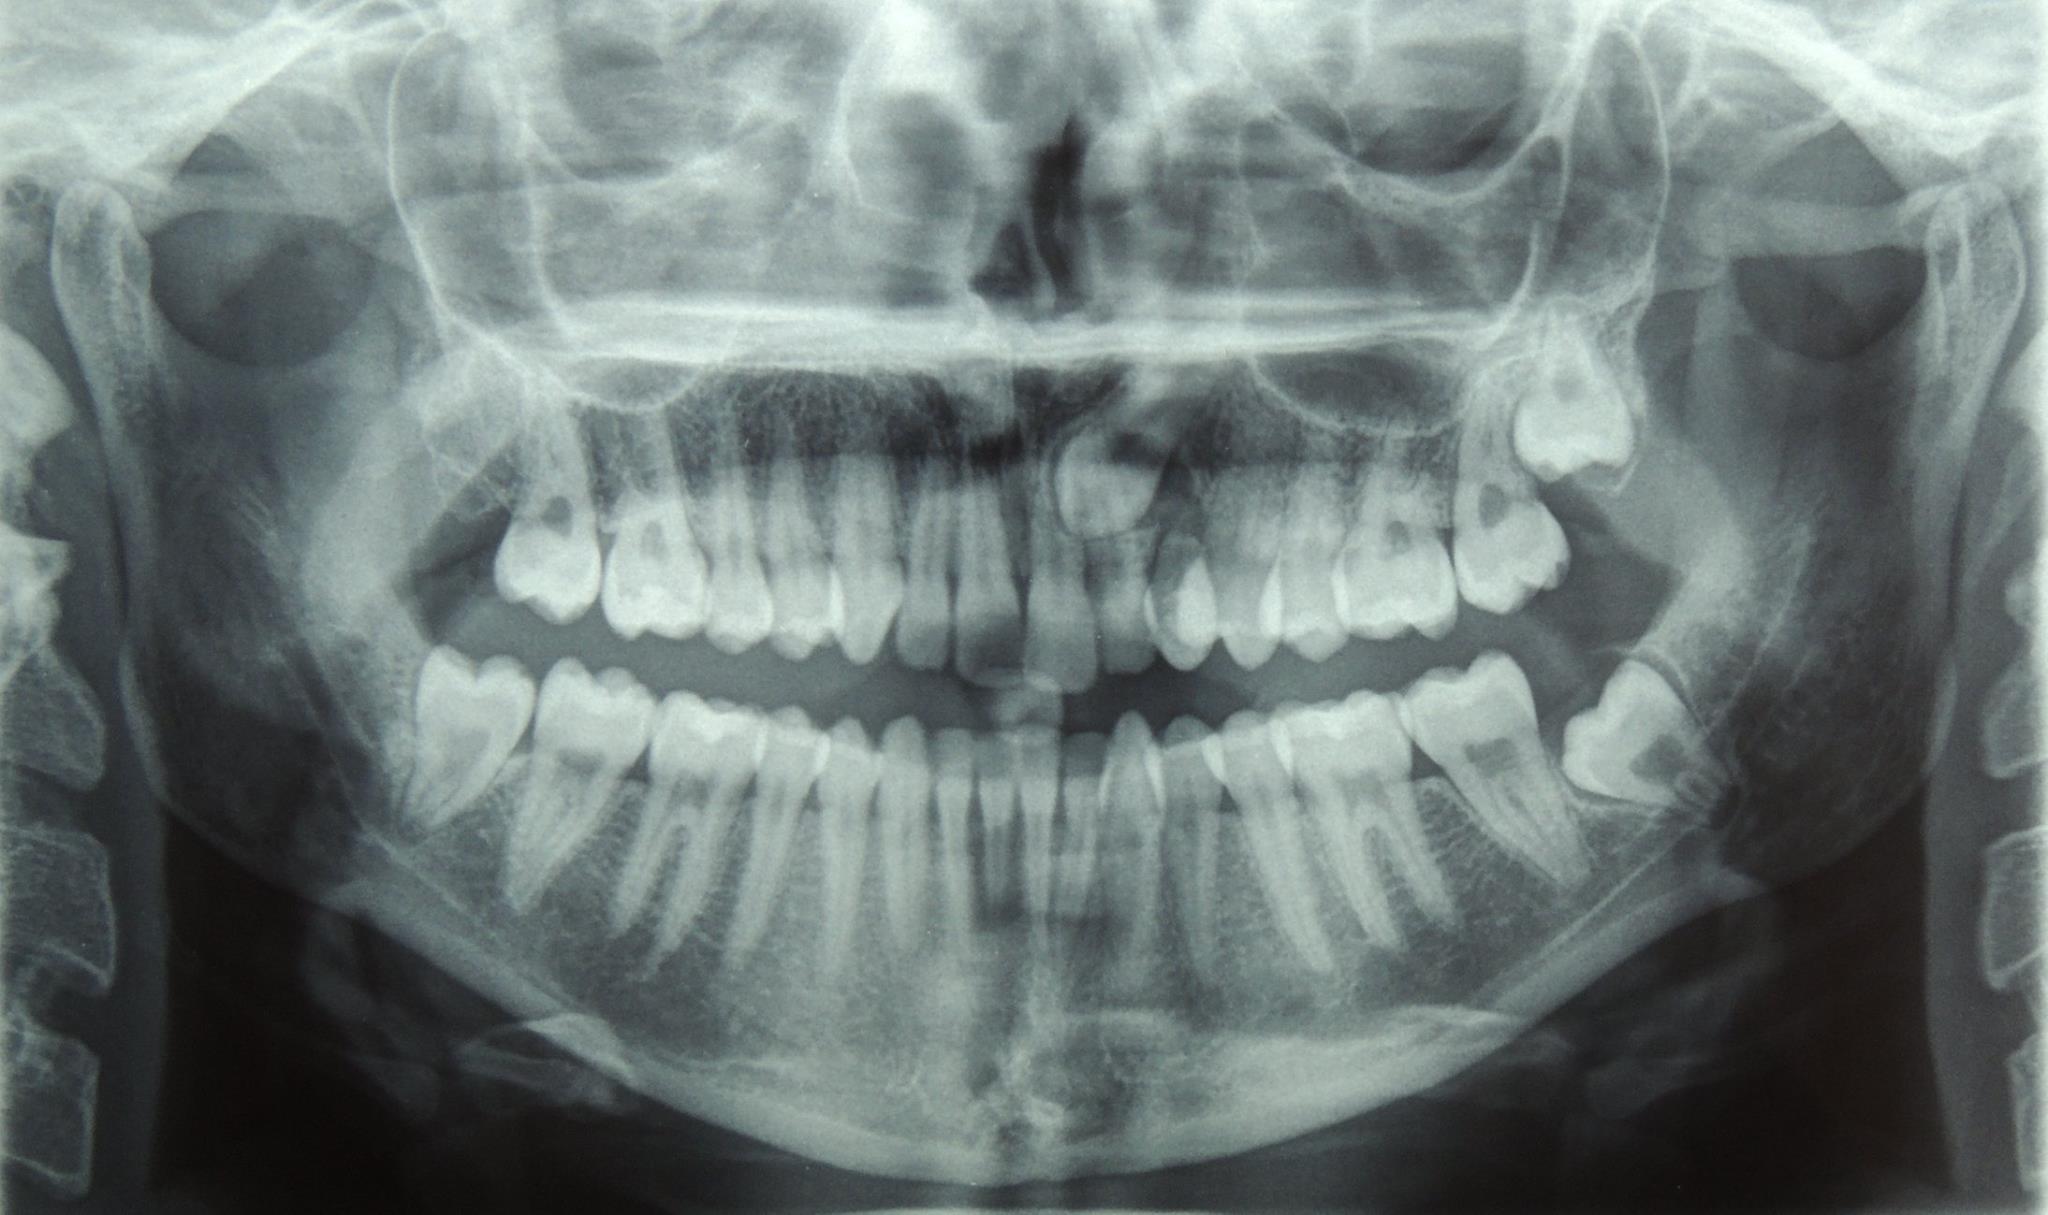

Canino in grave inclusione palatina